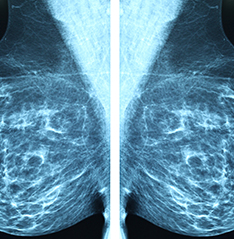

A mammogram is an X-ray of the breast. Mammograms also referred as mammography are commonly

used to screen for breast cancer. If an abnormality is detected on a screening mammogram, your doctor

may recommend a diagnostic mammogram to further evaluate that abnormality. In a diagnostic

mammogram, more x-rays are taken, providing views of the breast from multiple vantage points.To know more Click Here